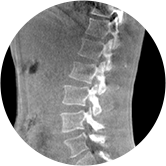

• 颈椎

• 腰椎

三维脊柱应用

精准诊断

手术方案规划

术后随访

• 脊柱评估

传统方法都是在二维平面,依靠棘突或椎弓根相对于椎体的偏移来评估脊柱侧凸。WR-3D可以更精准评估脊柱侧凸,制定手术方案,可以更直观地显示和量化椎体的平移和轴向旋转,术后评估更准确客观。

• 全身姿态评估

WR-3D能提供一种负重位状态下全身的姿态和三维空间任一平面平衡评估,使全脊柱术后评价更客观、真实 。通过各种临床参数包括骨盆、脊柱参数评价骨盆、脊柱平衡,避免由于髋膝屈曲造成的代偿性脊柱失衡的发生,WR-3D提供了三维空间任一平面平衡评估测量方法,可以更加定量地评估手术效果 。